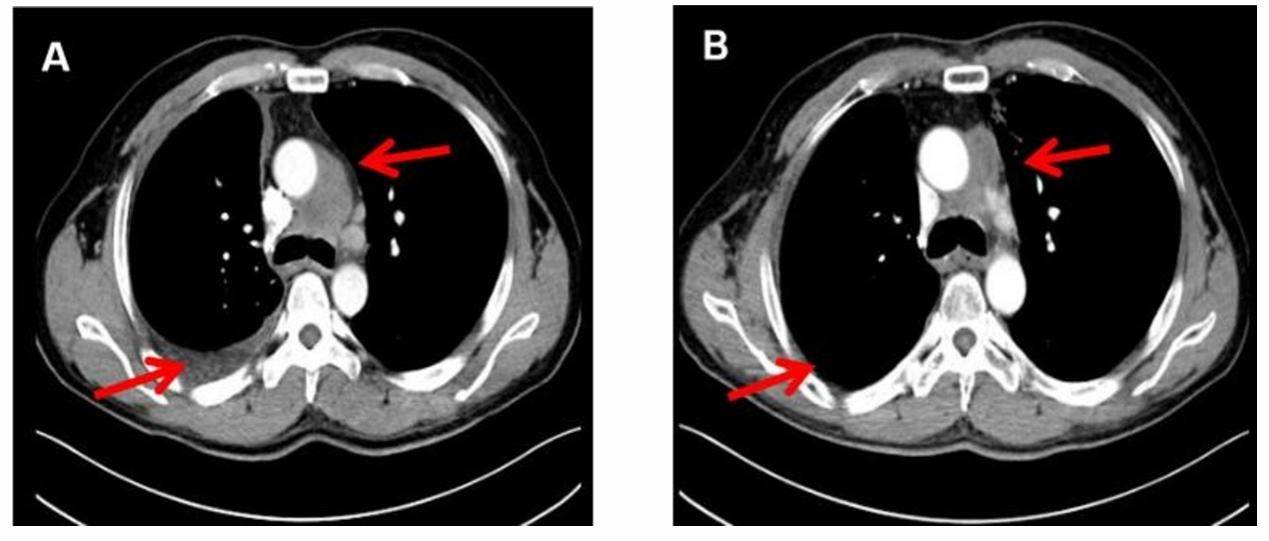

图1. 1例复发患者接受奥希替尼晚期一线再治疗的疗效评估

A:奥希替尼晚期一线治疗前基线CT扫描(2022年3月)显示纵隔淋巴结转移伴右侧胸腔积液

B:奥希替尼晚期一线治疗24个月后随访CT扫描(2024年4月)显示纵隔淋巴结较前缩小,右侧胸腔积液完全消退